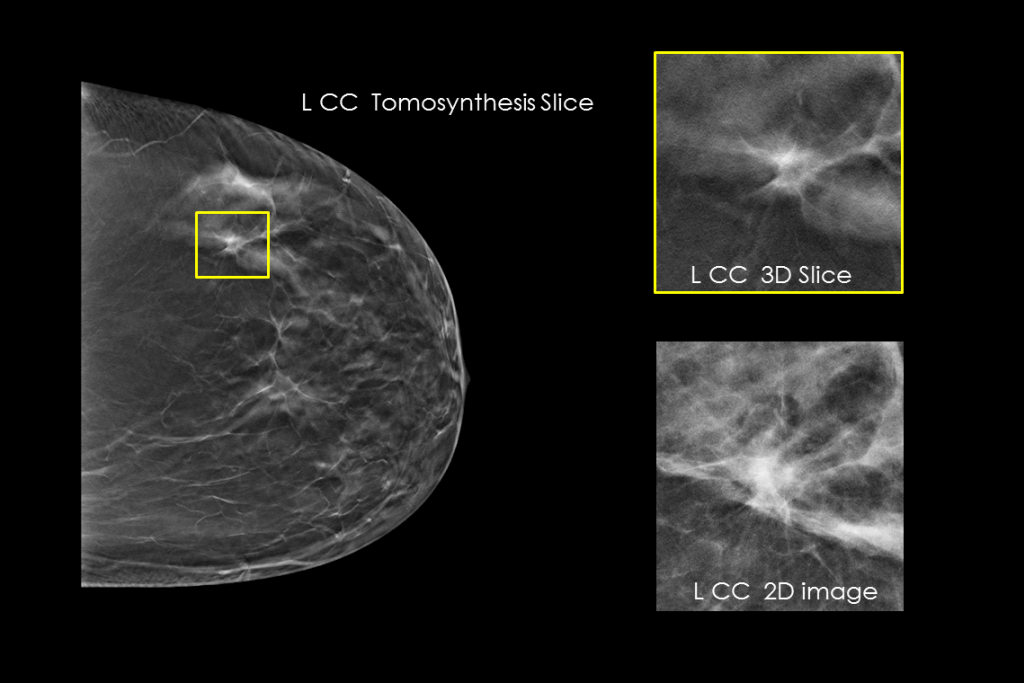

Klinische Aufnahmen einer Brustuntersuchung mit verdächtiger Läsion